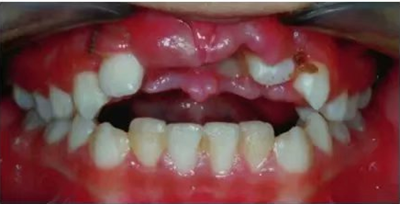

車禍后,一名10歲男孩被送往Shariati醫(yī)院急診科。診斷出上頜中切牙的脫落和側(cè)切牙的嵌入(圖1)。脫落的中切牙丟失了,沒(méi)有進(jìn)行再植。全景片示除第二磨牙外的恒牙列(圖2)。

圖1. 初診口內(nèi)照